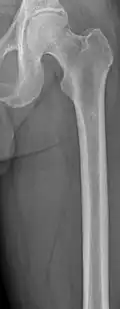

The diagnostic examination of a person with suspected multiple myeloma typically includes a skeletal survey. This is a series of X-rays of the skull, axial skeleton, and proximal long bones. Myeloma activity sometimes appears as "lytic lesions" (with local disappearance of normal bone due to resorption) or as "punched-out lesions" on the skull X-ray ("raindrop skull"). Lesions may also be sclerotic, which is seen as radiodense.[76] Overall, the radiodensity of myeloma is between −30 and 120 Hounsfield units (HU).[77] Magnetic resonance imaging is more sensitive than simple X-rays in the detection of lytic lesions. An MRI may supersede a skeletal survey, especially when vertebral disease is suspected. Occasionally, a CT scan is performed to measure the size of soft-tissue plasmacytomas. Nuclear Medicine Bone scans are typically not of any additional value in the workup of people with myeloma (no new bone formation; lytic lesions not well visualized on nuclear bone scan).

Femur with multiple myeloma lesions -

Same femur before myeloma lesions for comparison -